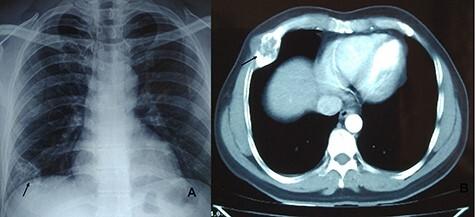

Rib tumors are rare. They can present with wide varieties of symptoms and differentiating benign from malignant lesions is challenging. A careful history and supporting investigations can help to reach the definite diagnosis. Surgical resection is the treatment of choice with excellent prognosis. A total of four patients were operated for the management of rib tumors over a period of 5 years at our institution. All four were benign lesions and included simple bone cyst, fibrous dysplasia with aneurysmal bone cyst, aneurysmal bone cyst and enchondroma. There were three male and one female. None of them is having recurrence till now. Surgical resection is the treatment of choice for benign rib tumors as it provides diagnostic and curative treatment.

肋骨肿瘤较为罕见。它们可表现出各种各样的症状,区分良性与恶性病变具有挑战性。详细的病史和辅助检查有助于明确诊断。手术切除是首选的治疗方法,预后良好。在我们机构的5年时间里,共有4例患者接受了肋骨肿瘤手术治疗。所有4例均为良性病变,包括单纯骨囊肿、伴有动脉瘤样骨囊肿的纤维发育不良、动脉瘤样骨囊肿和内生软骨瘤。其中男性3例,女性1例。至今无一例复发。手术切除是良性肋骨肿瘤的首选治疗方法,因为它兼具诊断和治疗作用。